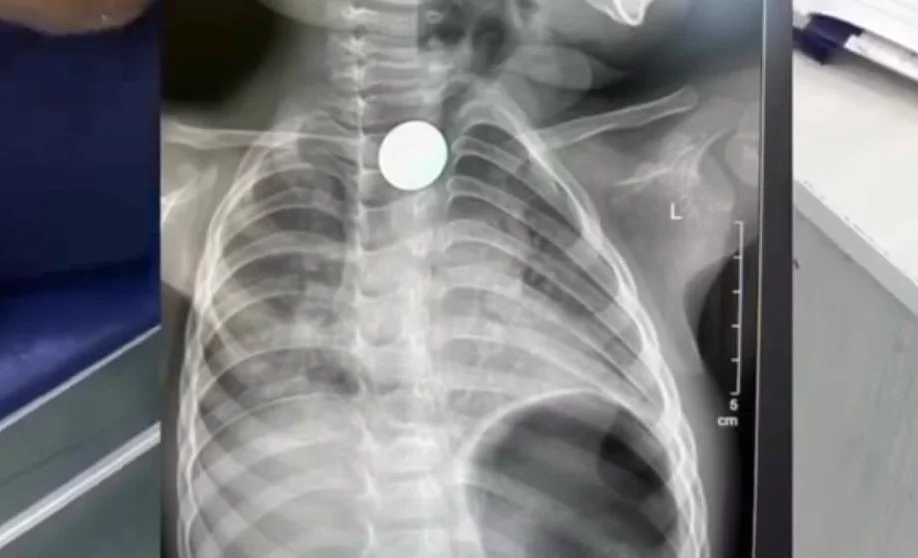

Бишкек, 08.04.26 /Кабар/. №3 шаардык медициналык тез жардам балдар клиникалык ооруканасынын дарыгерлери 2 жаштагы баланын кызыл өңгөчүнөн тыйынды операциясыз алып чыгышты. Бул тууралуу аталган ооруканадан билдиришти.

Маалым болгондой, кызыл өңгөчүнө тыйын тыгылып калган наристе Нарындан Бишкекке жөнөтүлгөн. Бөтөн зат кызыл өңгөчтүн экинчи физиологиялык тар жерине туруп калгандыктан, аны буга чейинки үч ооруканадан алып чыга албай коюшкан.

Ал эми тез жардам балдар клиникалык ооруканасынын дарыгерлери тыйынды операциясыз, Фолея катетерин колдонуу ыкмасы менен алып чыгышты. Учурда баланын абалы жакшы. Ал дароо үйүнө чыгарылып, өз алдынча тамактанып калды.